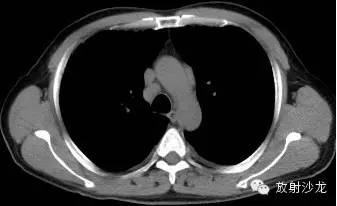

第三例:

51岁男性,体检发现肺门、纵隔、腹腔淋巴结肿大,CT拟诊结节病,后于北京协和医院确诊。

第1—3图显示Garland三联征。第4图显示腹腔淋巴结肿大。